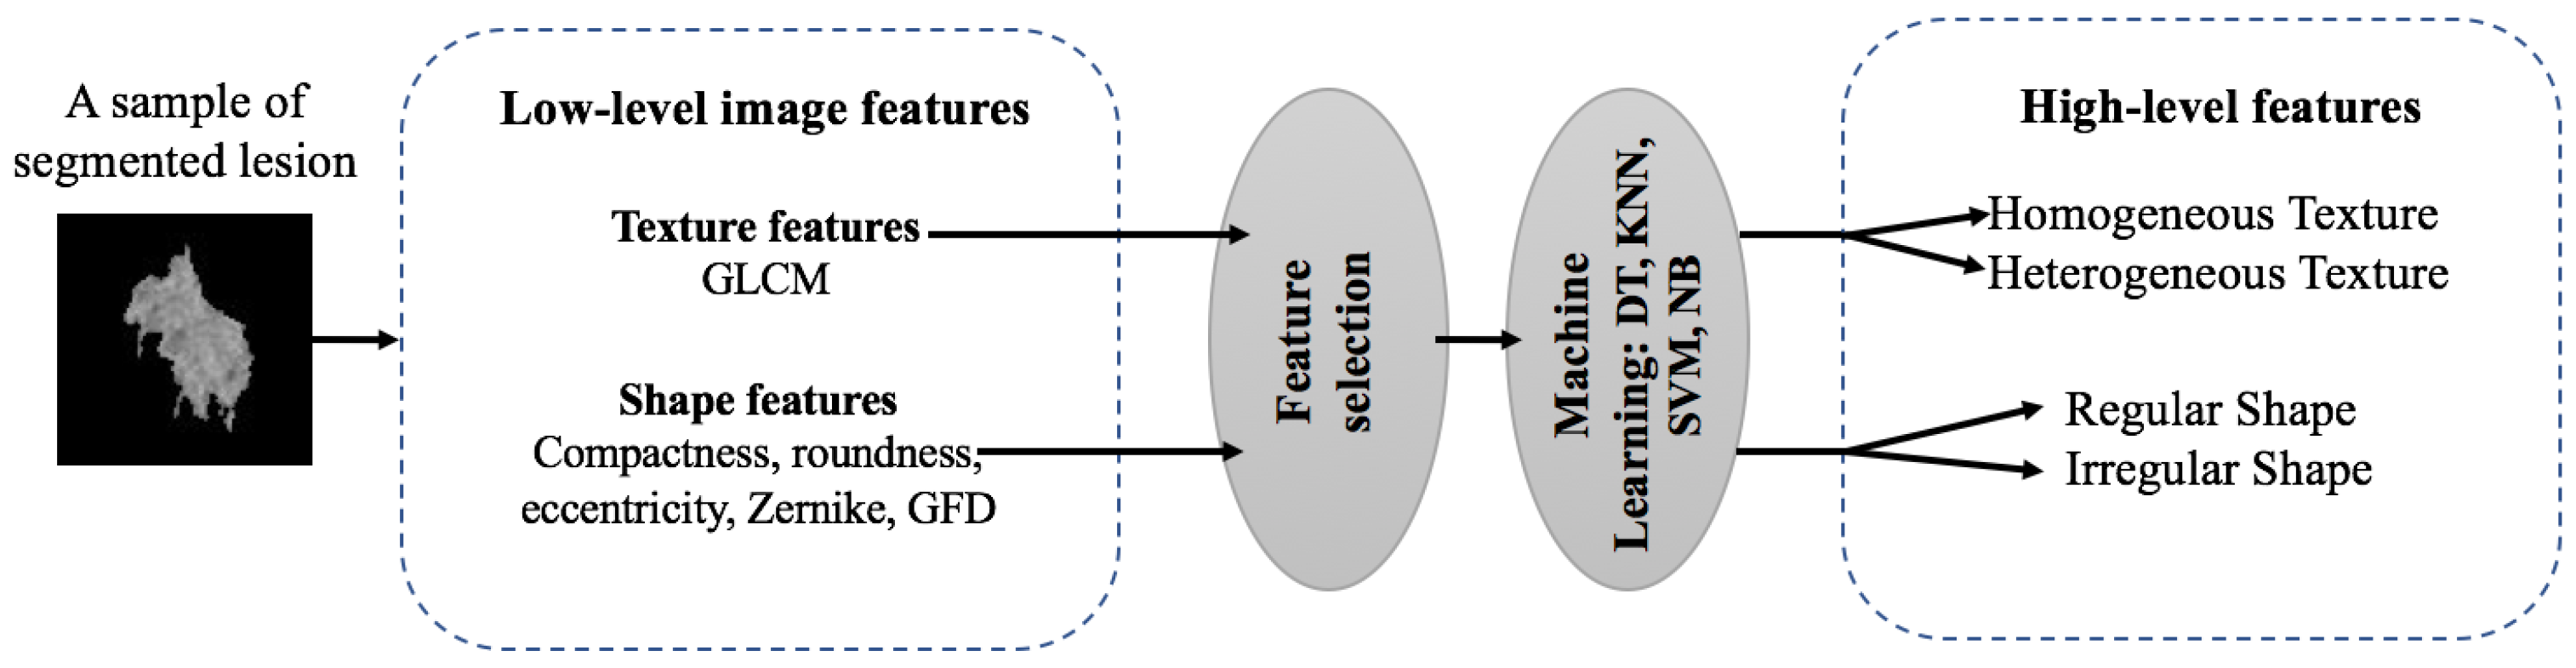

2.2. Feature Extraction

2.5. Image Annotation

3.4.2. Texture Annotation

3.4.3. Shape Annotation